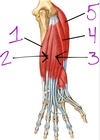

1. pronator teres

2. FCR

3. FCU

4. palmaris longus

5. FDS